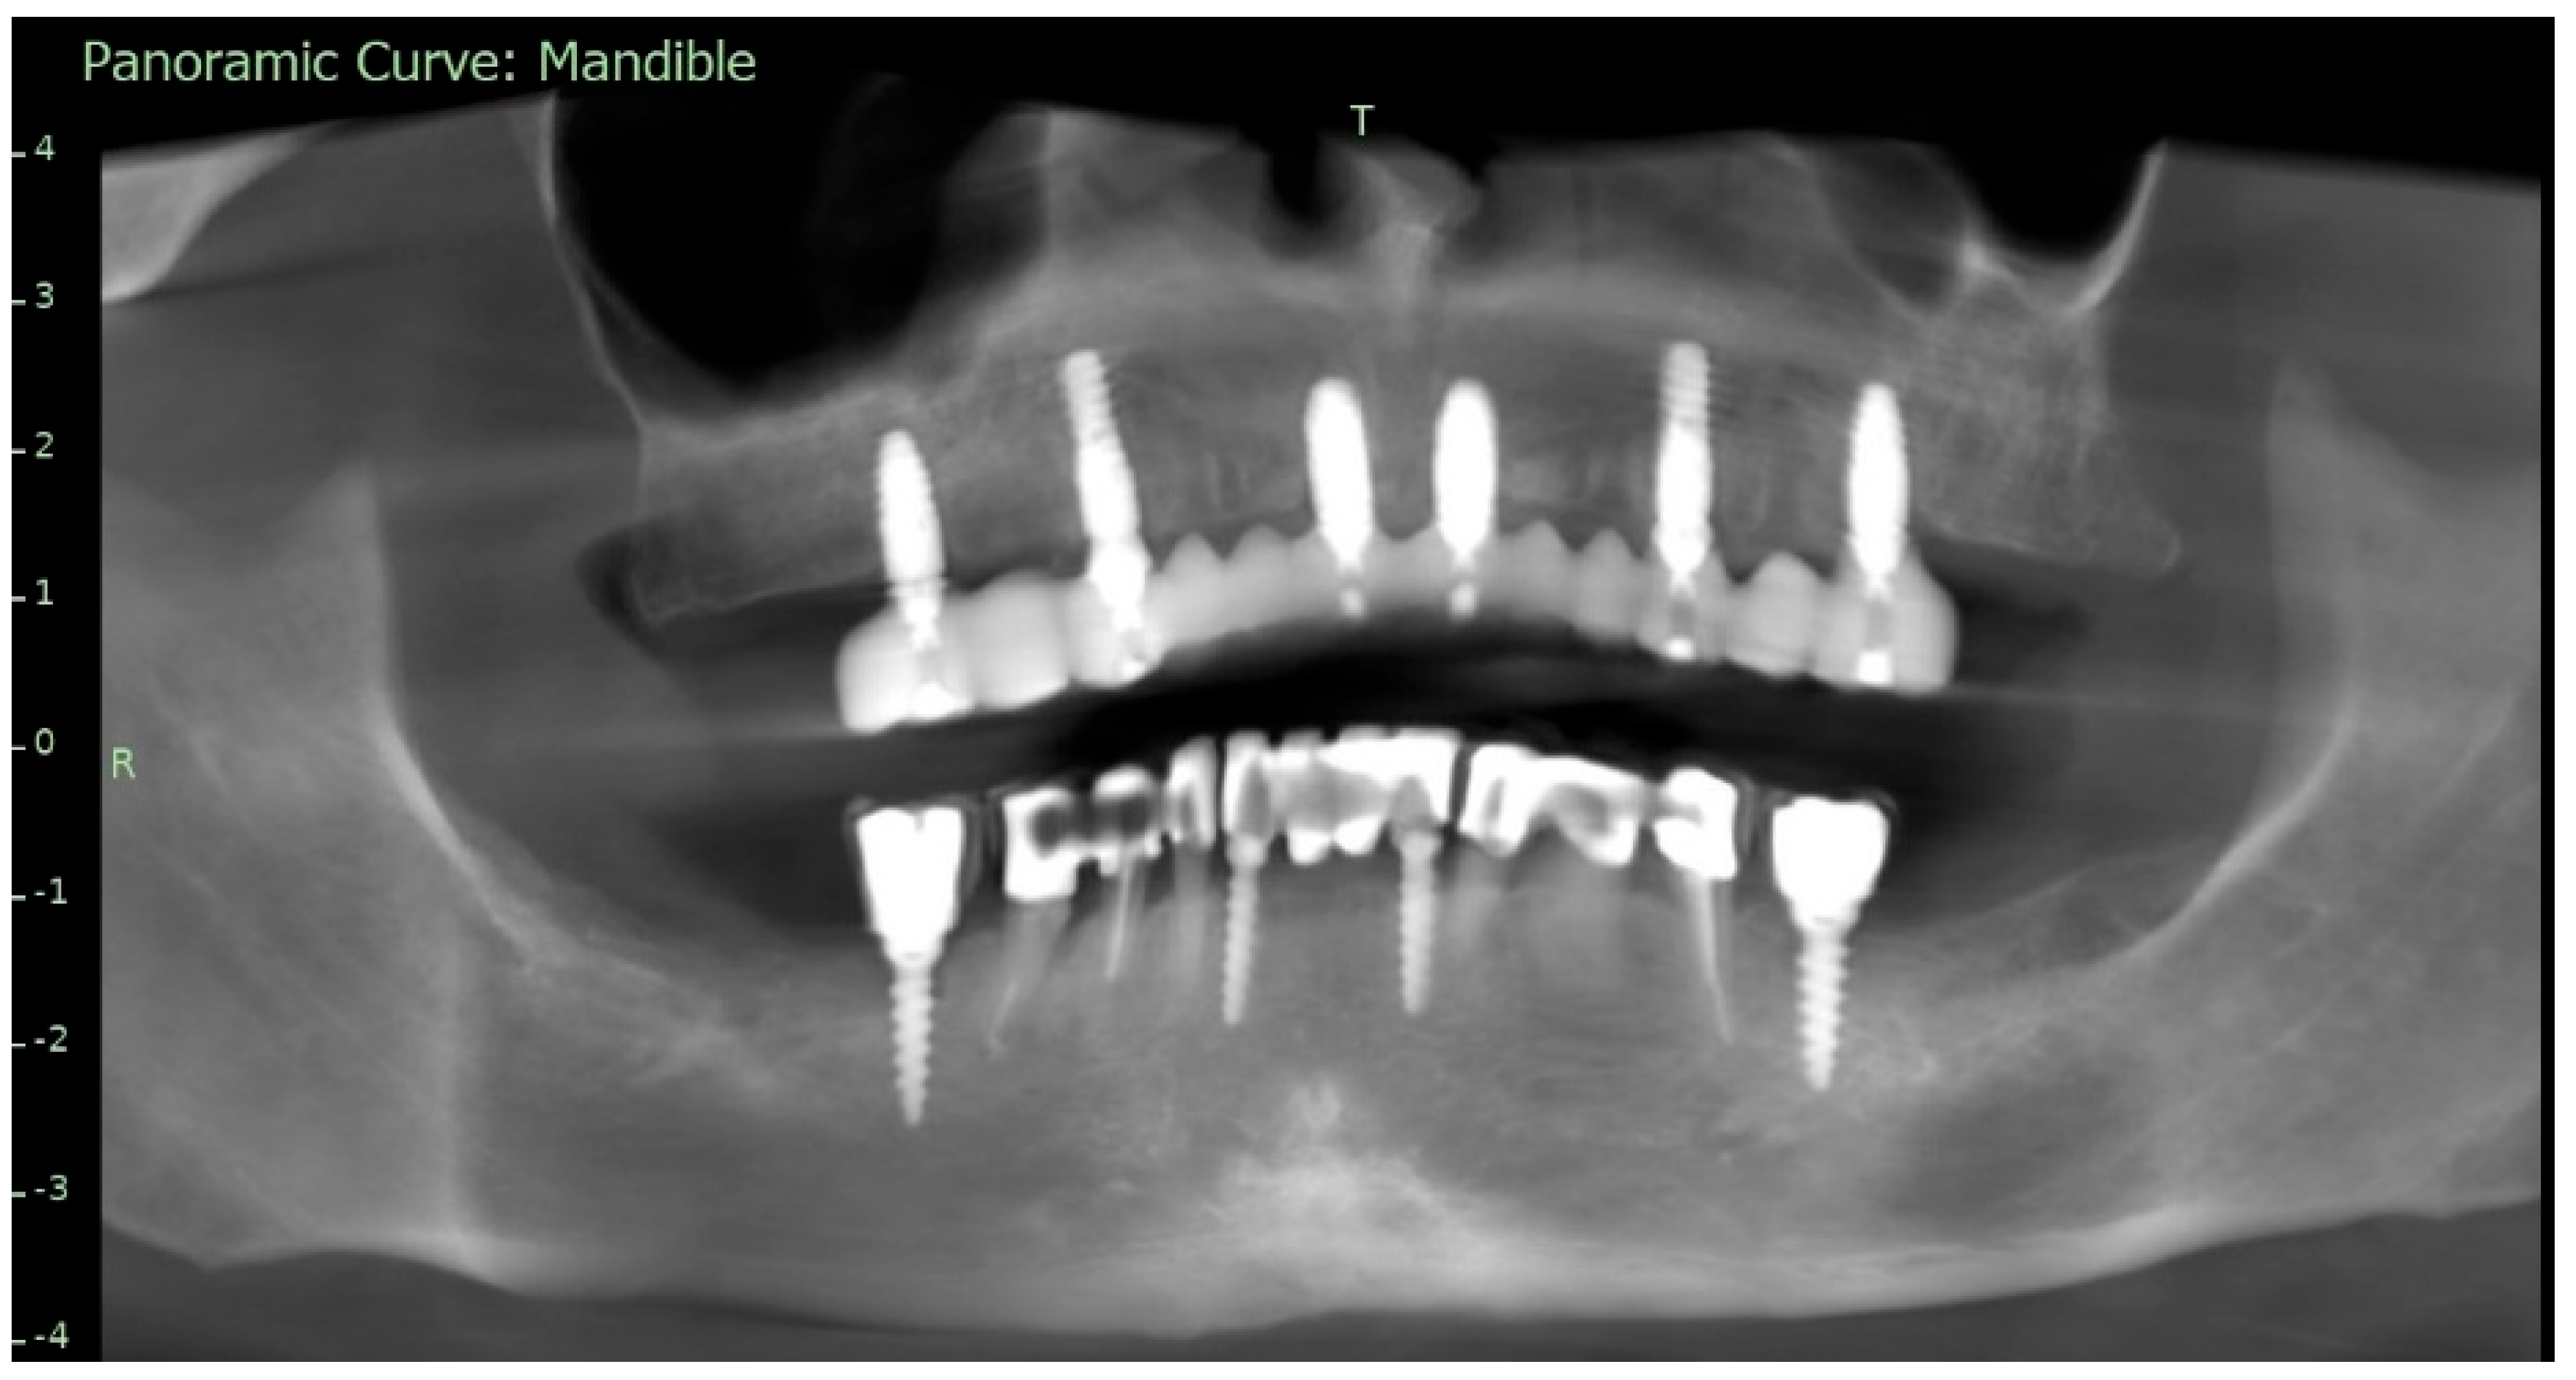

To supplement the clinical findings, a cone beam computed tomography (CBCT) scan was obtained (Figure 1) and evaluated. The implants existing in the maxilla demonstrated proper surrounding bone architecture. The compromised status of the remaining teeth was confirmed. In addition, the available bone conditions in the regions of teeth 14 and 24 were assessed to be adequate for future implant placement, particularly in the context of immediate implant insertion. This is in accordance with the literature emphasising that sufficient bone volume, labial plate integrity, and socket morphology, are critical prerequisites for successful immediate implant placement [7,8,9].

Figure 1. Preoperative panoramic reconstruction from CBCT, showing the initial condition of the existing tooth- and implant-supported restorations in the maxilla and mandible, as well as the visualisation of two planned implants in positions 14 and 24.